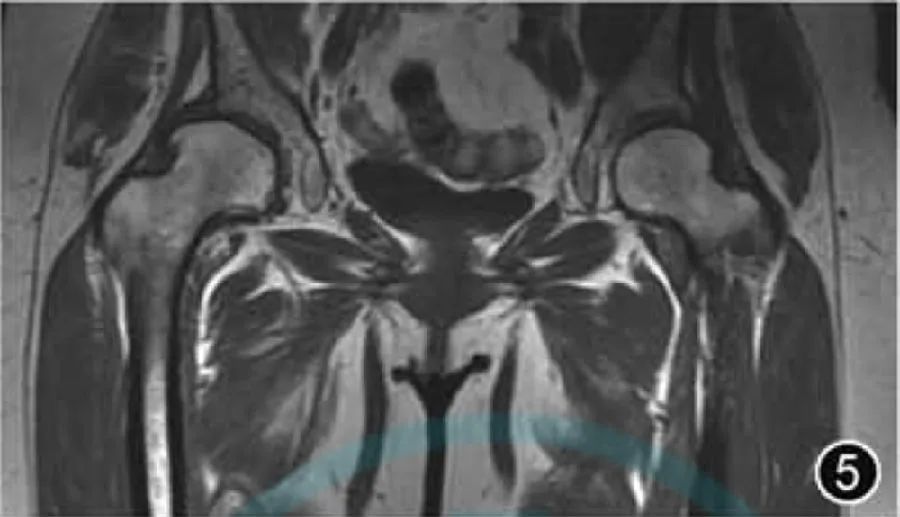

4.DDH: DDH – это заболевание, связанное с аномальным развитием головки бедренной кости и вертлужной впадины (рис. 5), в основном из-за относительно мелкой вертлужной впадины, что приводит к недостаточному охвату головки бедренной кости, что, в свою очередь, приводит к аномальному распределению нагрузки на суставы, нестабильности суставов, повреждение хряща и вторичный ОА тазобедренного сустава. Радиологи должны быть знакомы со структурами вертлужной кости, хрящей, связок и мягких тканей у младенцев и детей раннего возраста. При использовании МРТ для оценки ДДГ они должны оценивать ретроверсию диспластической вертлужной впадины и степень задержки оссификации. Головку бедренной кости можно обнаружить через оба бедра. Сравните и оцените. Основным преимуществом МРТ является возможность более точно визуализировать хрящевую вертлужную впадину и определить ее охват головки бедренной кости, чем обычные рентгенограммы. Поскольку у маленьких детей трудно определить центр головки бедренной кости, для оценки ДДГ на МРТ можно использовать остеоацетабулярный индекс и хондроацетабулярный индекс. Следует отметить, что при легкой ДДГ результаты измерения углов упоминать не нужно.

Рисунок 5. МРТ-изображение дисплазии тазобедренного сустава. Корональный Т1-ВИ демонстрирует несоосность суставной поверхности между вертлужной впадиной и головкой бедренной кости, а покрытие головки бедренной кости правой вертлужной впадиной значительно уменьшено.